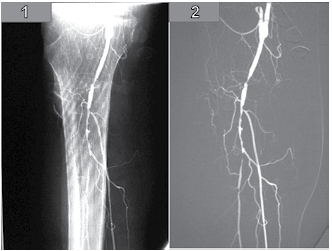

Observe a sequência das imagens a seguir.

(Fonte: Arquivo pessoal da Banca Elaboradora)

A técnica de manipulação de imagens digitais utilizada no exame foi: